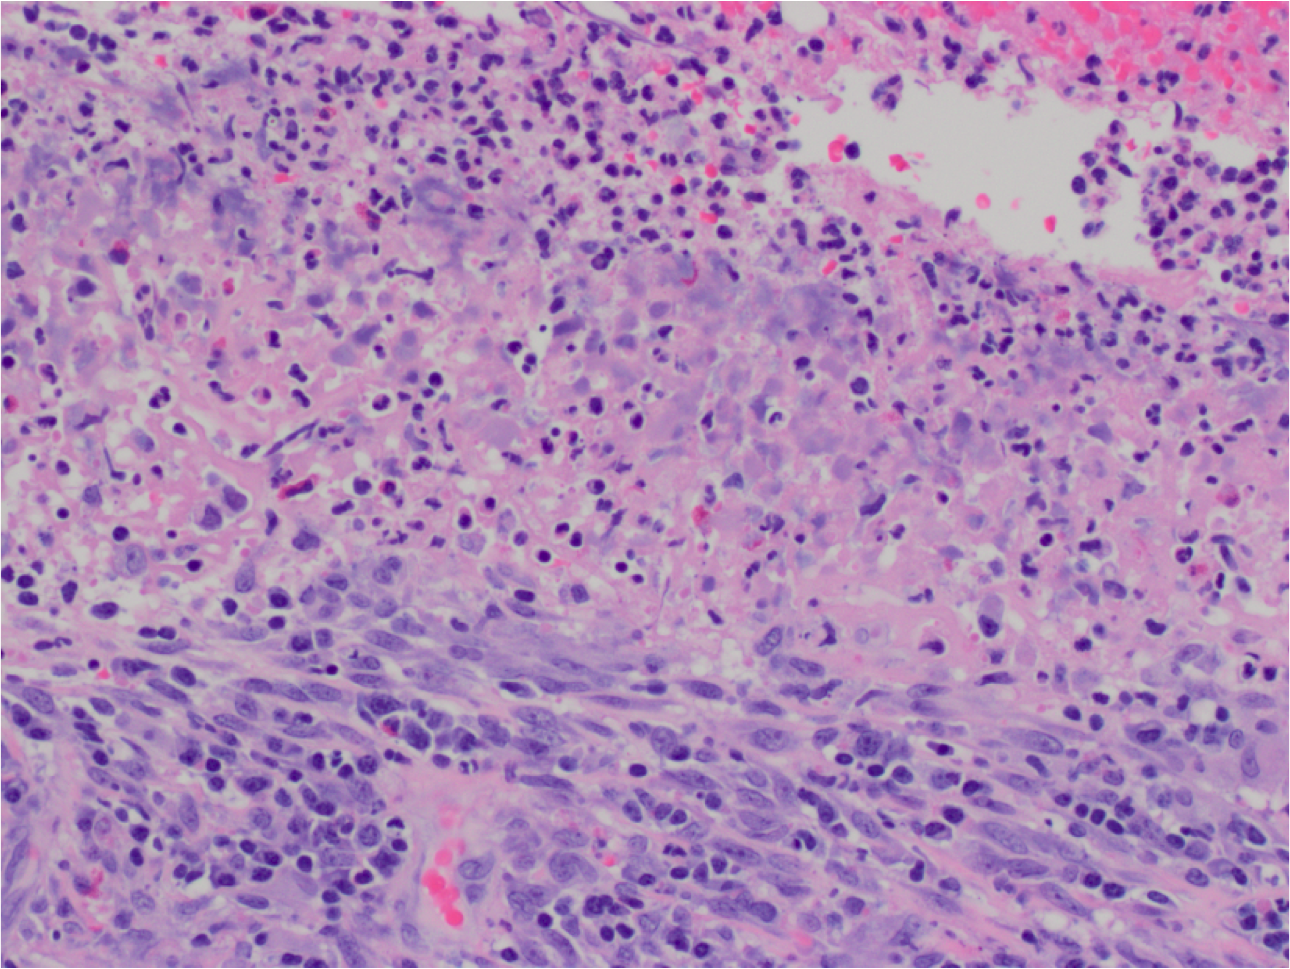

What’s this?

Gastric Ulcer

Mucosal denudation (left) with fibrinopurilent exudate (top), necrosis, and underlying granulation tissue.